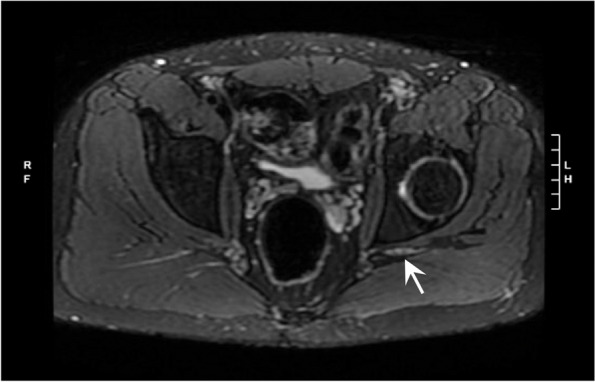

The patient was also seen by pain management specialists, and other possible diagnoses were considered, including radiculopathy and complex regional pain syndrome. Magnetic resonance (MR) imaging of the lumbar spine on POD 42 showed left L5-S1 disk extrusion with nerve compression but left L5, S1 foraminal steroid epidural injections were performed without relief. The patient’s hyperesthesia led to the consideration of complex regional pain syndrome, although no vasomotor or sudomotor symptoms were noted. On POD 52, a lumbar sympathetic nerve block (0.25% bupivacaine) along with a distal ankle block (1% lidocaine with 0.375% bupivacaine) were performed, and they provided significant pain relief. Ongoing diagnostic uncertainty prompted MR neurogram from the lumbar spine to the foot on POD 67, which showed neuritis in the sciatic nerve distribution starting in the pelvis (above the level of surgery, thigh holder, tourniquet, and nerve blocks). This was consistent with a diagnosis of post-surgical inflammatory neuropathy (Fig. 2). At this time, the patient was experiencing improved pain control after adjustment of a variety of neuropathic and narcotic pain medications over his postoperative course. He also had improved function and weight-bearing on the operative extremity with ongoing physical therapy. On 1-year follow-up, the patient had significant improvement with near resolution of symptoms, with a pain regimen consisting of duloxetine and diclofenac.

Fig. 2.

Magnetic resonance neurogram showing asymmetric T2 hyperintensity and enlargement of the left sciatic nerve